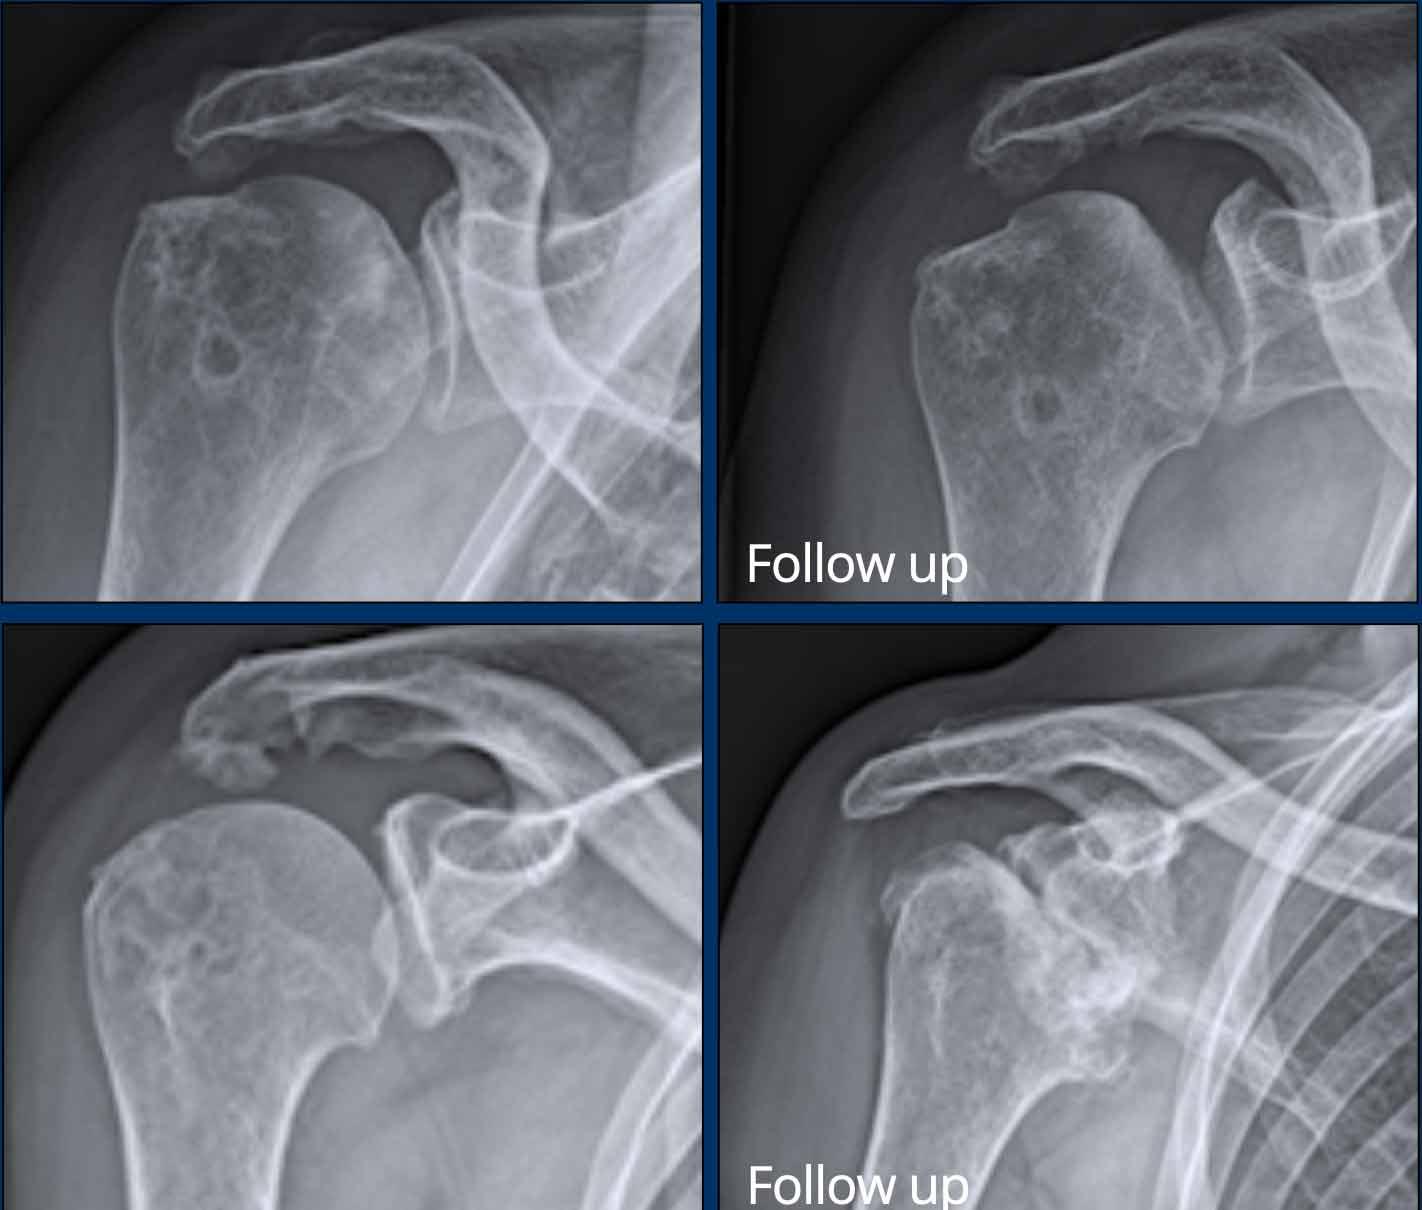

Bào mòn xương lớn tại đầu trên xương cánh tay, ổ chảo và mỏm cùng vai ở bệnh nhân viêm khớp tự phát thiếu niên.

Hình ảnh của bệnh nhân hemophilia có tràn máu khớp vai tái phát.

Có các dấu hiệu của viêm khớp thoái hóa thứ phát với xơ cứng xương dưới sụn và hình thành gai xương ở cả hai phía của khớp ổ chảo – cánh tay.

Nhìn chung, bệnh khớp do hemophilia có nhiều điểm tương đồng với viêm khớp thoái hóa.

Tuy nhiên, sự hiện diện của các tổn thương bào mòn, hình thành nang xương dưới sụn lan rộng và tiền sử tràn máu khớp tái phát là những đặc điểm phân biệt giúp hướng đến chẩn đoán bệnh khớp do hemophilia.